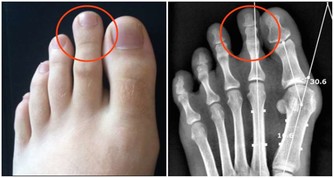

有人會將青筋都和靜脈曲張聯繫在一起,如果是靜脈曲張,會比較直觀也非常明顯,同時還會伴有很多異常表現。

除了手部,腿上也容易出現青筋,這種情況不要忽視,有可能是靜脈曲張的預兆,尤其是過度勞累和久坐以及久站的人需要多加註意。不要總保持一個姿勢,要適當活動活動,改善一下血液循環。